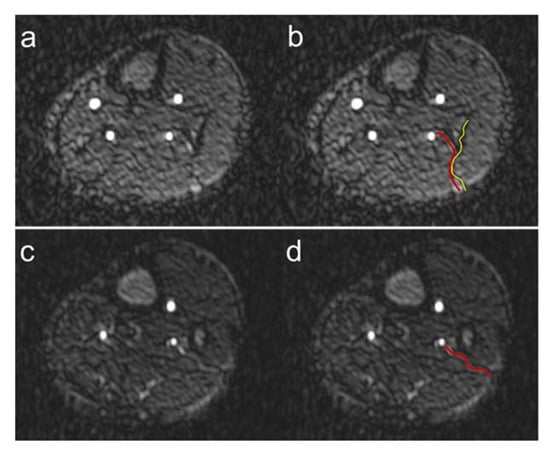

We were unable to detect fibular perforators in a total of 11 patient legs. In 4 of these 11 legs, fibular grafting was performed without subsequent graft failure, although the perforators were not visible. For this reason, we hypothesize that despite the excellent image quality, the already very high spatial resolution, and the predominant absence of artifacts of QISS-MRA, not all anatomically present fibular perforators, especially very small ones, can be detected. In the future, the use of even higher spatial resolution QISS-MRA pulse sequences, e.g., at 3T MRI, would be useful in this regard. QISS-MRA can distinguish between purely septocutaneous, purely musculocutaneous, and between fibular perforators, which mainly run within the septum and have a short course in muscle [6]. The typical course of the purely septocutaneous fibular perforators in the posterolateral intermuscular septum could be visualized by QISS-MRA (Figure 8).

Figure 8.

Course of fibular perforators. Exemplary course of a septocutaneous fibular perforator in the posterolateral intermuscular septum (a) in a 62-year-old male patient. The red line in panel (b) shows the course of the perforator, the yellow line the posterolateral intermuscular septum. Exemplary course of a septocutaneous fibular perforator to the cutis (c) in a 49-year-old male patient. The red line in panel (d) shows the course of the perforator to the cutaneous level.

Although the purely septocutaneous perforators are preferred for fibular transplantation because they are easier to harvest and do not require muscle resection, all three forms of fibular perforators are candidates for transplantation. For this reason, we did not distinguish between the three different types of perforators in our work. As shown in Figure 8, QISS-MRA can be used to follow the course of the perforators to the cutis in many cases. When this is not the case, it is probably because the perforators, like all vessels, taper in the periphery and become too small to detect.